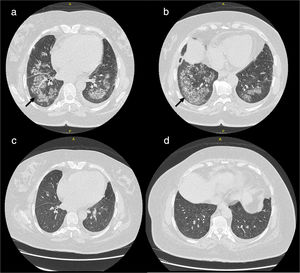

Cases presentationsCase 1A 52 year-old female patient presented with fever, anorexia, intense myalgia and weight loss during 2 months. The onset was associated was painful swollen hand joints, knees and ankles. She developed pulmonary symptoms in the form shortness of breath, chest pain, cough and orthopnea. The patient mentioned that six months before her other complaints started she had developed nasal symptoms with rhinorrhea, formation of nasal crusts and sores, which were diagnosed as allergic rhinitis. Initial laboratory investigations showed elevated markers of inflammation ESR 1st hour and CRP levels, normal liver function tests and normal serum creatinine levels and further investigations confirmed the presence of c-ANCA associated GPA. High-resolution computed tomography (HRCT) showed extensive pulmonary infiltrates (Fig. 1). The patient received oral corticosteroids (prednisolone) in a dose of 30mg/day/po combined with MMF in a dose of 2g/day/po. One month after the start of the treatment she showed much improvement of the constitutional manifestations, respiratory symptoms and laboratory markers of inflammation. The repeated HRCT showed almost complete resolution of the pulmonary infiltrates (Fig. 1). The dosage of prednisolone could be tapered over six months to 5mg/day/po and the dose of MMF was kept the same. During one year of follow up there were no signs or symptoms of disease relapse.